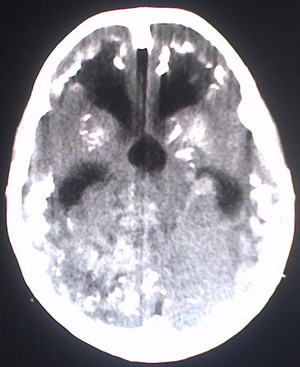

以下是引用jiajie在2009-2-3 20:02:00的发言:[br]脑室周围白质区可见大量斑片状钙化,部分融合成带状,双侧侧脑室及第三脑室扩大。[br]考虑弓形体原虫感染。(先天性宫内感染、torch综合症)

以下是引用lkc8963在2009-2-3 21:15:00的发言:[br]临床眼睑可见静脉扩张,ct双侧眼上静脉亦示扩张,颅内钙化以皮层\\软脑膜为主而不是位于白质和室管膜,再加上静脉窦异常,还是应该考虑静脉血管瘤病,可能为较复杂的血管畸形.

以下是引用卜一在2009-2-4 9:21:00的发言:[br]sturge-weber综合征:面部三叉神经分布区的毛细血管性或海绵状血管瘤以及同侧枕、顶或额叶软脑膜的血管瘤(以静脉性为主)。脑皮质,特别是第二三层,毛细血管可有增厚和钙化。局部发生层状坏死、神经细胞脱失、萎缩、胶质细胞增生及钙盐沉着。可根据面部典型分布的特征性皮痣作出诊断。头颅ct:发现面部血管瘤同侧的脑内病理钙化影,呈双层线条波浪形、脑回形或树枝形。本例支持:sturge-weber综合征![br]